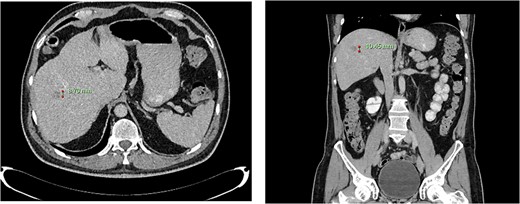

Computed tomography dated 12 March 2013 of the abdomen and pelvis measuring 8.70 mm (anterior–posterior) lesion at liver segment 5/6 in axial (left) and coronal (right) view.

Subsequent surveillance imaging including magnetic resonance imaging and CT scans demonstrated gradual reduction and eventual complete resolution of the liver metastases (refer to Figs 1–4). Furthermore, routine colonoscopy and a positron emission tomography (PET) scan revealed no evidence of locoregional cancer recurrence nor distant metastatic disease present; essentially rendering the patient cured from an initial diagnosis of metastatic rectal cancer. It has been at least a decade since his initial diagnosis and the patient remains in remission.